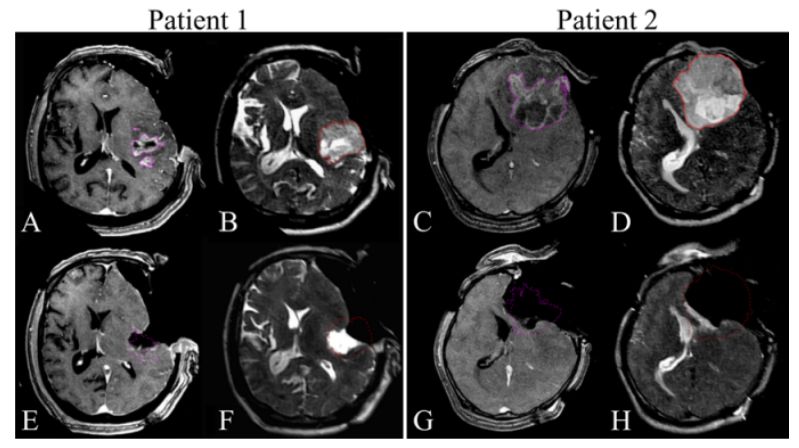

6.多毛症合并颅内黑色素瘤1例报道

Hypertrichosis lanuginosa acquisita associated with intracranial melanoma: case illustration.

PMID: 28707995 DOI: 10.3171/2017.2.JNS162723.

本文首次在文献中报道1例多毛症(Hypertrichosis lanuginosa acquisita, HTLA)合并颅内黑色素瘤病例,临床表现、影像图片、术中所见如下图所示。

【周川】